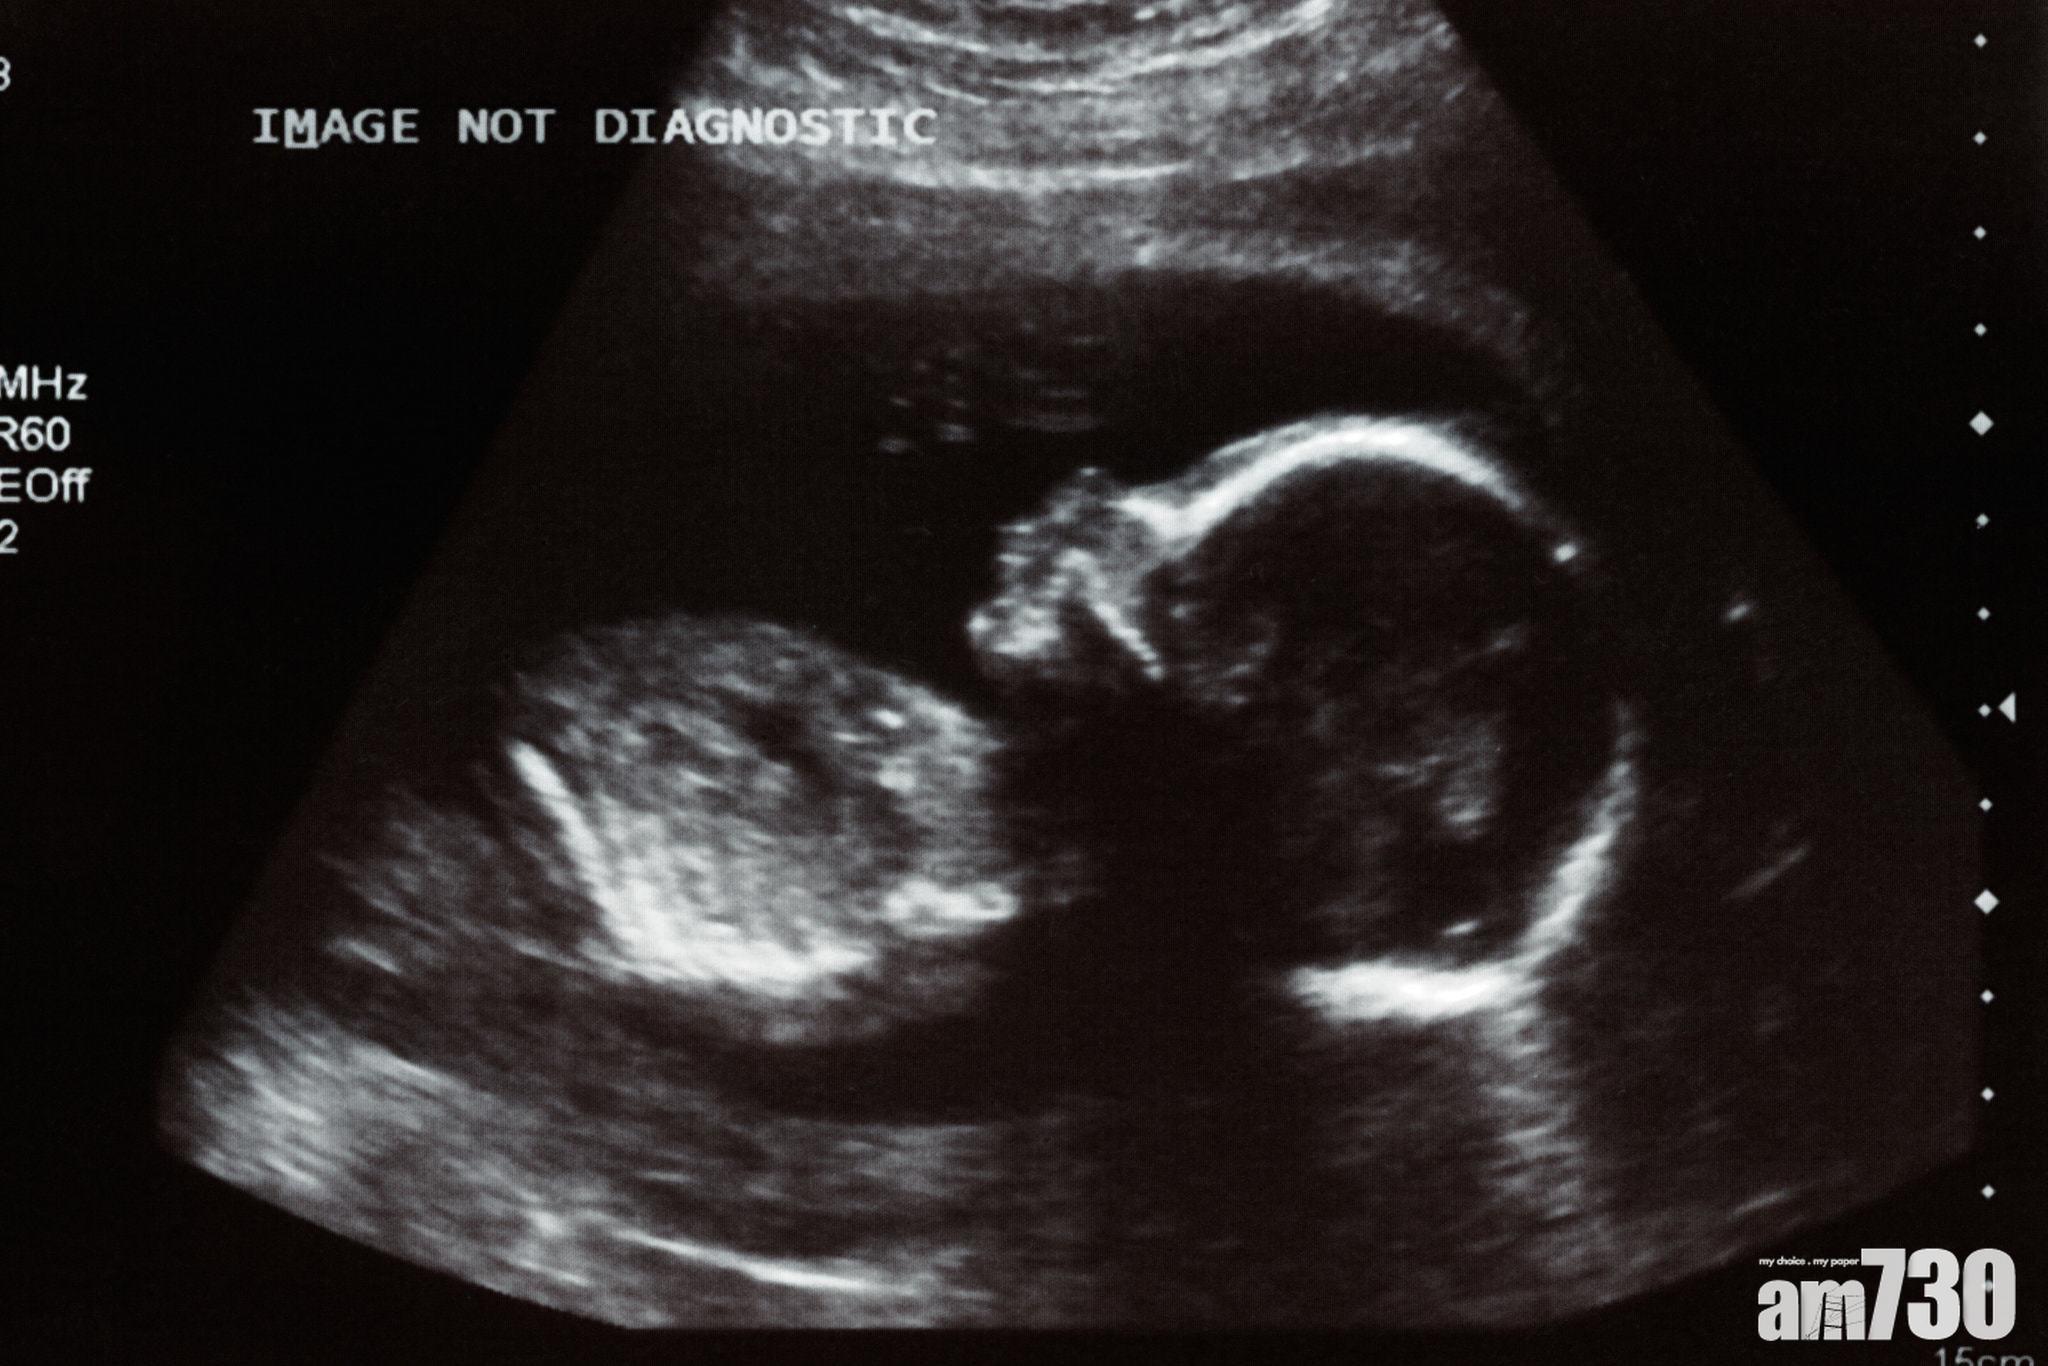

研究首次證實胎兒可從母體染疫。(資料圖片)

一份周二在國際科學期刊《自然通訊》(Nature Communications)發表的報告,首次證實胎兒可在母親子宮內感染新冠肺炎,醫生相信病毒經由胎盤傳播。